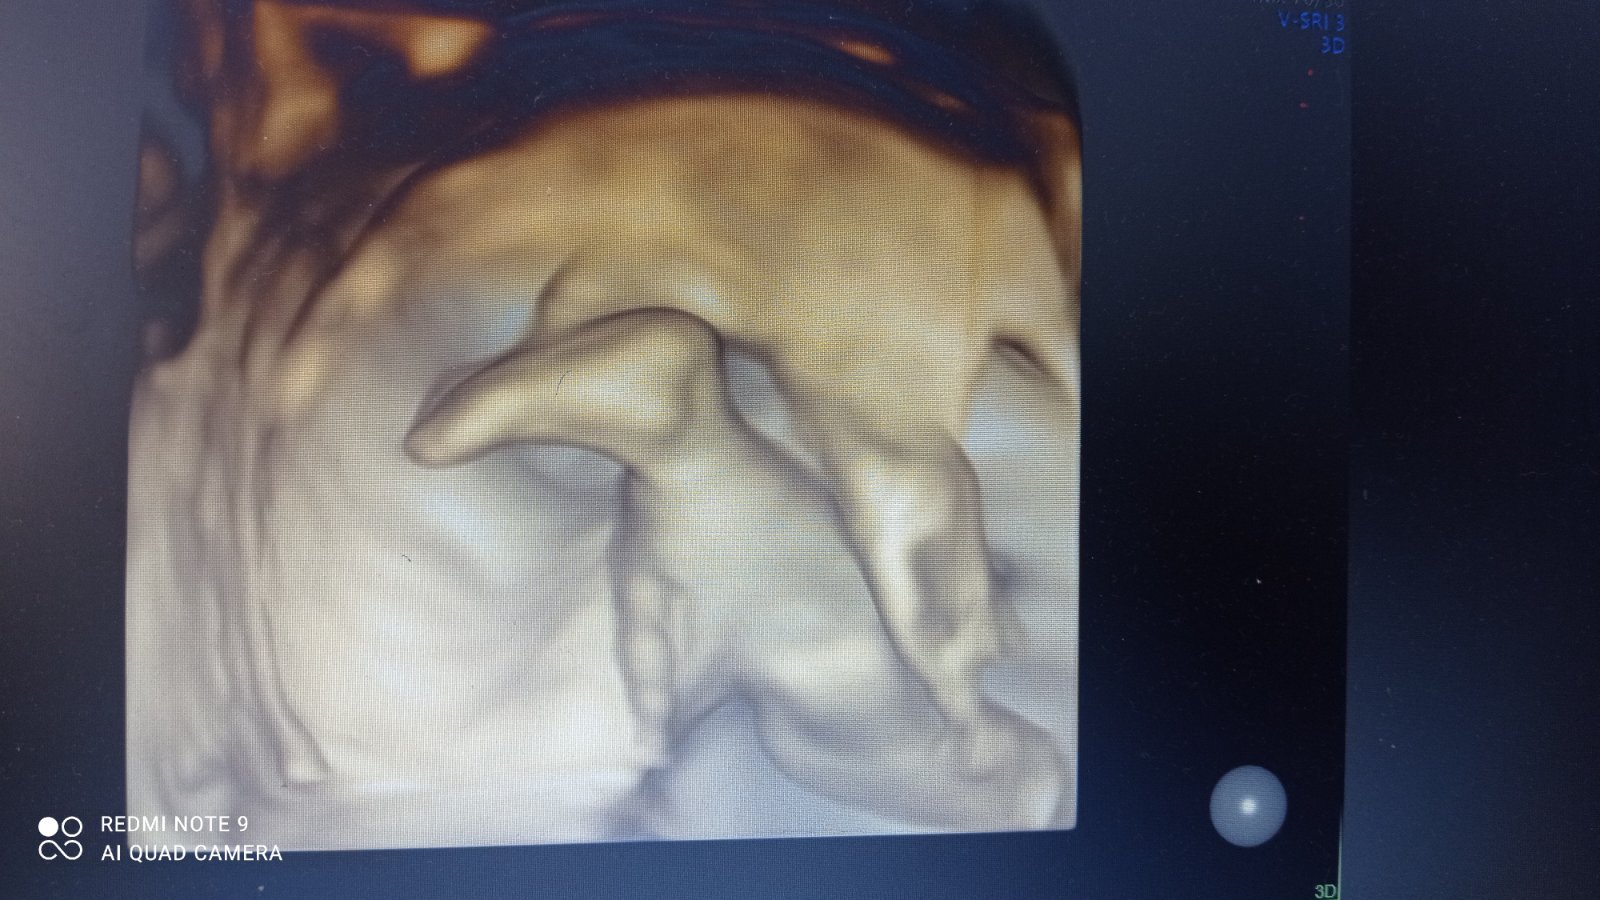

No na psychiku je to obrovská záťaž, 2 neúspešne Inseminácie a prvé dve IVF dopadli katastrofálne, vždy sme mali len 1 embryo 😕 v prvom sa na chvilku ujalo, ale nakoniec z toho bolo biochemické teh. a pri druhom vôbec nič. Ako kebyže mame na začiatku všetky vyšetrenia spravené tak sme sa tomu mohli vyhnúť. Teraz tretie IVF v MT 5 embryi, poslali sme ich aj na genetiku do Prahy a vrátili sa nám 2 zdravé, 2 patologické a 1 take na hrane, že skôr nie ako ano. A keď budem mat teraz v utorok na kontrole všetko ok, tak jedno z nich budeme vkladať tak už sa teším 😊

@evinku to plne chápem, aj pre mna je to veľmi ťažké. My sme prvýkrát navštívili car v polke augusta 2021…a od vtedy stále na niečo čakáme. Verim, že už tentokrát to bude úspešne 😊 ja sa cítim lepšie, volala som za výsledky, tak že to mám v poriadku, iba mám dobrat predpísané lieky a malo by to byt ok tak smäd aj bude 🙂 a utorok ma teda potom čaká vklad teším sa aj sa bojím.